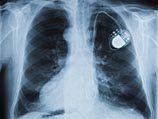

Кардиостимуляторы, помогающие регулировать сердечный ритм, стали настоящим спасением для многих пациентов с заболеваниями сердечно-сосудистой системы, однако постоянная необходимость заряжать аккумулятор ограничивает использование этого метода лечения, так как замена батареи требует хирургического вмешательства.

Инженер Адриан Зурбахен из Бернского университета (Швейцария) нашел решение этой проблемы, разработав устройство на основе часового механизма с автоматическим заводом, разработанного для карманных часов швейцарской марки Abraham-Louis Perrelet в 1777 году.

По аналогии с тем, как часы заряжаются при движении по запястью благодаря заводу пружины, часовой механизм в кардиостимуляторе может генерировать электрический ток, используя движения сердечной мышцы. Для этого необходимо, чтобы он находился непосредственно на сердце.

Экспериментальная система была успешно протестирована на свиньях, у которых удалось добиться устойчивого сердечного ритма 130 ударов в минуту. По данным отчета Адриана Зурбахена, исследование находится на ранней стадии, и сроки клинических испытаний на человеке пока не установлены.